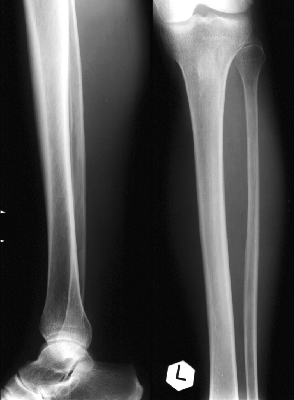

ДЕ ВИ БАЧИТЕ КІСТКУ, ЩО РОЗТАШОВАНА З ЛАТЕРАЛЬНОЇ СТОРОНИ ГОМІЛКИ?

варіанти відповідей